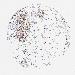

BRCA TCGA BRCA VALIDATION PROTEIN EXPRESSION